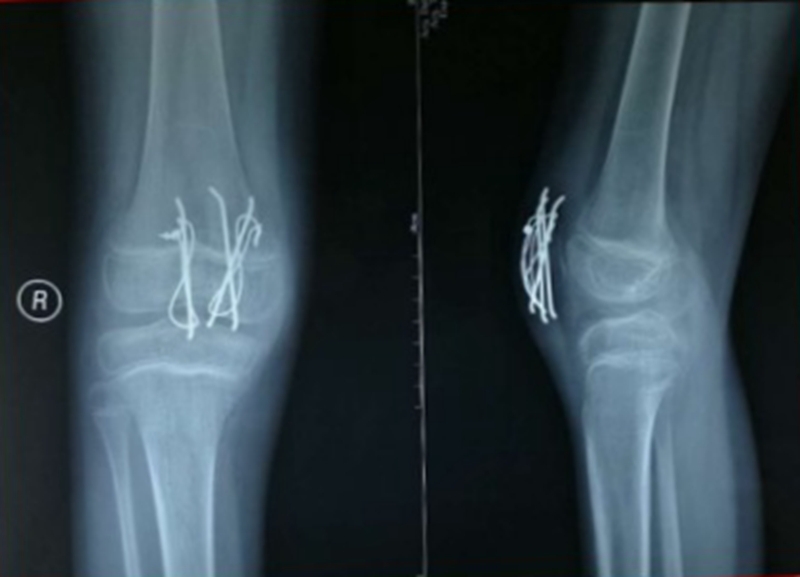

图7 术中X线

图8 术后石膏固定X线

手术关键点在于恢复伸膝装置的连续性,争取解剖复位,并修复髌旁支持带。如果术中因股四头肌腱挛缩出现复位困难,则一期行股四头肌腱延长术。

手术采取腰麻,在止血带下进行。行膝前正中切口,电刀止血。